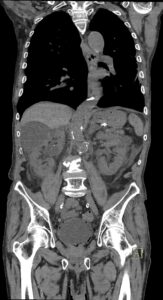

Figurile 4 şi 5: coronal examinare CT abdomen şi pelvis fără substanță de contrast

Discuţie caz nr 131: pacient de 85 de ani cunoscut diabetic este adus la camera de gardă pentru dureri abdominale difuze, efectueaza CT fără substanță de contrast deoarece eGFR este 21 mL/min/1.73 m². Se evidențiază pericardita în cantitate medie, mai multe chiste renale – unul spontan hiperdens, multiple plăci aterotrombotice calcificate la nivelul aortei și ramurilor precum și multiple bule aerice în peretele vezicii urinare și conținut hidro-aeric al vezicii urinare. Ultimele două elemente sugerează diagnosticul de cistita emfizematoasă.